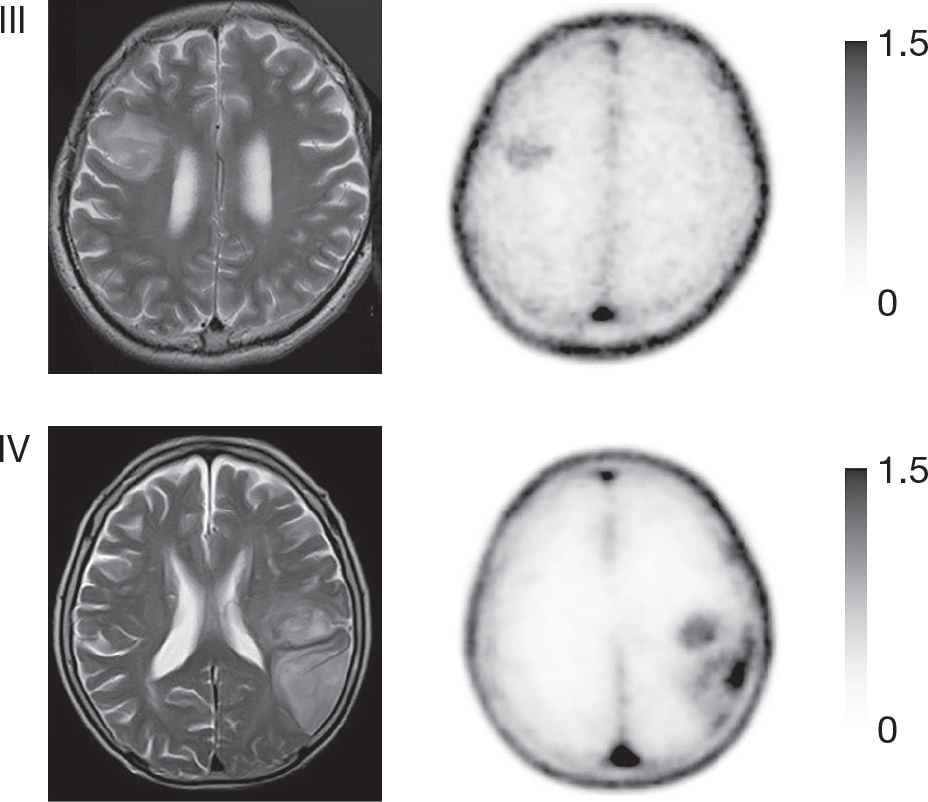

PET AGENTS TARGETING CELL CYCLE PROGRESSION

All four nucleoside-based agents – 18F-FLT, 11C-4DST, 18F-FMAU and 11C-TdR – are based on thymidine, which pairs with adenine in the DNA double helix and is therefore directly involved in cellular proliferation. These agents use equilibrative nucleoside transporter 1 (ENT1) to enter cells (Figure 5). Although ENT1 is present throughout the brain including endothelial cells (Table 3), none of these agents can readily cross the BBB leading to a high T/N ratio. In clinical practice, uptake of either agent will therefore reflect at least increased BBB permeability next to ENT1 overexpression (105). After entering the cell, most become phosphorylated by thymidine kinase 1 (TK1), which is cell-cycle dependent and therefore upregulated in tumor cells, or TK2, which is restricted to mitochondria and is cell-cycle independent. Only 18F-FLT and 11C-4DST interact with TK1: 18F-FLT subsequently becomes trapped in the cytoplasm because it lacks an essential hydroxyl group, causing uptake to indirectly reflect increased cellular proliferation, while 11C-4DST becomes incorporated into DNA, thereby directly reflecting increased DNA synthesis and proliferation (Figure 5) (105). Kinetic analyses will be necessary to distinguish uptake due to disrupted BBB from that due to increased cellular proliferation(106), decreasing their sensitivity for brain tumor cells compared to amino acid agents like 11C-MET and 18F-FET (Figure 6), and they should not be used for e.g., recurrent non-enhancing brain tumors (107, 108). However, uptake of 18F-FLT has been shown to differentiate between grade III and IV gliomas, and is sometimes seen in non-enhancing areas on MRI, suggesting not all uptake is BBB-related; it has also been suggested that even a small number of glioma cells can cause BBB disruption without additional contrast agent leakage (108, 109). Tumor uptake of 18F-FLT can also be used to predict tumor progression in meningiomas (110). Background uptake of 11C-4DST is paradoxically high compared with 18F-FLT, and it has not been studied much (111). 18F-FMAU becomes phosphorylated by TK2, raising the question whether uptake really reflects cellular progression, while 11C-TdR is not used anymore because of its high catabolism into 11C-CO2 which causes significant background uptake.

Fig 6

Figure 6. T1-weighted post-contrast (cT1), T2-weighted (T2), 18F-FLT PET ([18]F-FLT) and 18F-FET ([18]F-FET) images of a patient with a non-enhancing glioblastoma, WHO grade IV. The lesion is hyperintense on the T2-weighted image but does not show contrast enhancement. Increased uptake in the T2-hyperintense region can clearly be seen on the 18F-FET PET image, but there is no uptake visible on the 18F-FLT PET image, illustrating the drawback of PET agents that cannot easily cross the BBB. This figure is reproduced – with new figure legend appropriate for current article – from Nowosielski et al. (2014), Figure 1, under the terms of the Creative Commons Attribution 4.0 International (CC BY) License (http://creativecommons.org/licenses/by/4.0) (107).